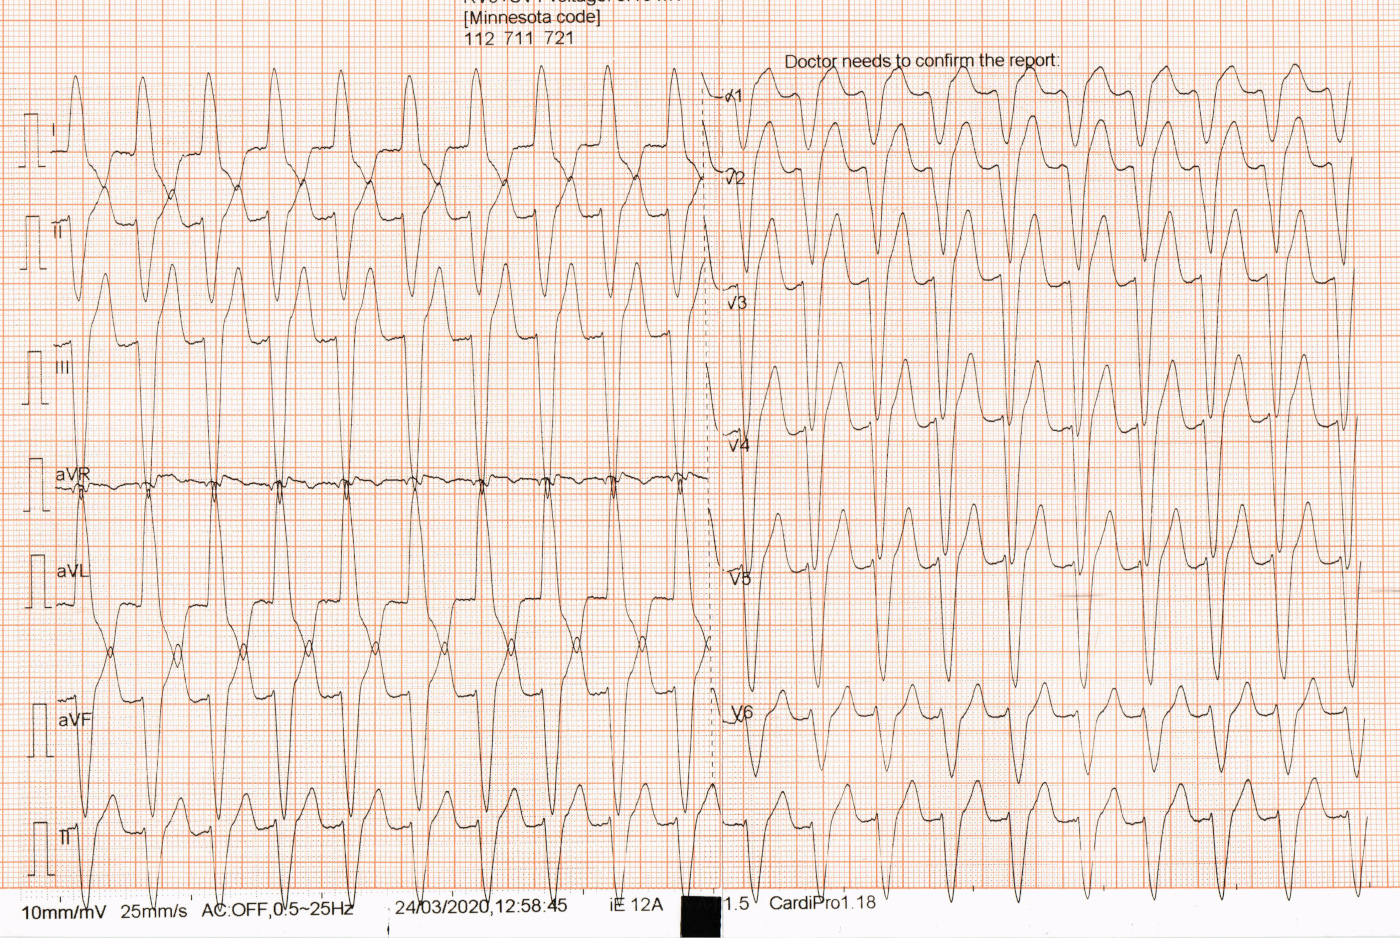

52 M with palpitations

vt_ecg.jpg

Dissociated, slower sinus rhythm

vt_ecg_m.jpg